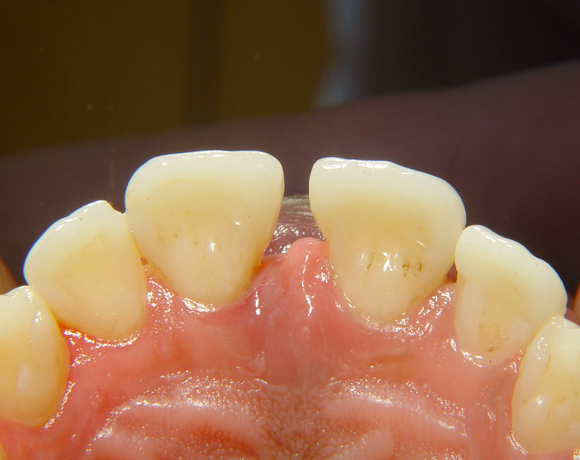

Diese Frontzahnsituation stellte den Behandler vor größere Probleme

Durch Abrasion der Seitenzähne wurden die Frontzähne nach labial verdrängt und lückig. Nach Verlust des Zahnes 41 entstand eine Lücke in der drei Zähne Platz fanden. Auch im Oberkiefer wurden die lateralen Lücken mit Veneers verkleinert.